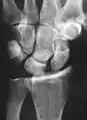

Dynamic instability: Increased scapholunate distance (between yellow lines) upon ulnar deviation of the wrist, but not otherwise.